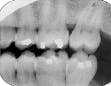

The bisecting-angle technique creates specific errors in vertical angulation, giving shortened images (see Radiograph 2 as an example of foreshortening) or lengthened images (see Radiograph 3 as an example of elongation). Substantially shortened images occur because there is too much vertical angulation. This causes distortion in the reproduction of the actual size of the tooth. The solution requires a decrease of the vertical angulation by at least 10 degrees.

Conversely, lengthened im-ages occur because there is not enough vertical angulation. Another reason is that the film is curved in the mouth. Increasing the vertical angulation by at least 10 degrees and repositioning the film to prevent bending will alleviate this distorted image.